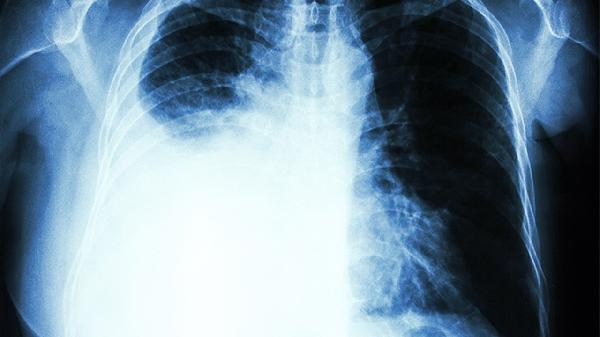

15岁肋骨一边凸起可能与脊柱侧弯、佝偻病、外伤、肋骨发育异常或胸廓畸形等因素有关。建议及时就医,通过影像学检查明确诊断。

先天性肋骨融合或分叉畸形可能导致局部隆起,通常无疼痛症状。CT可显示肋骨形态异常,影响呼吸功能时需手术切除畸形肋骨段。

漏斗胸或鸡胸可能伴随单侧肋骨突出,与遗传性结缔组织发育异常有关。严重者需行Nuss手术或胸骨翻转术矫正,轻度可使用真空吸盘保守治疗。